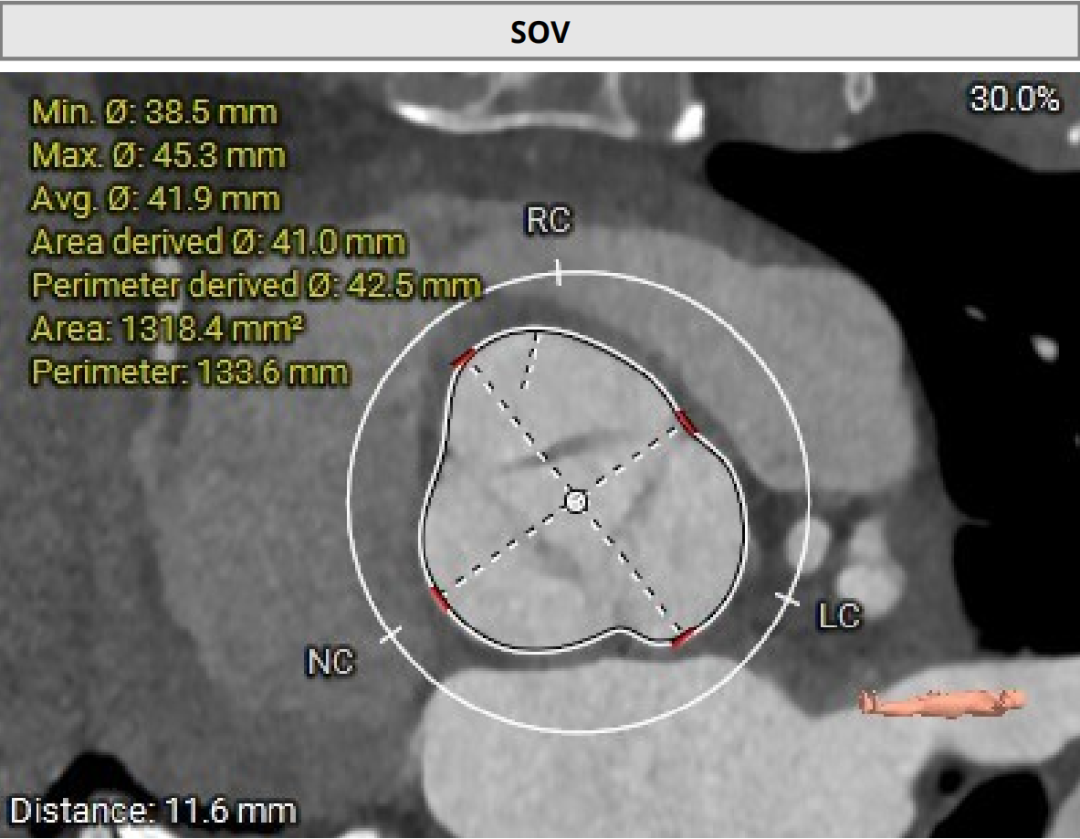

2026年伊始,TaurusTrio经导管主动脉瓣系统在复旦大学附属中山医院,浙江大学医学院附属第二医院,中国医学科学院阜外医院,首都医科大学附属北京安贞医院,四川大学华西医院等多家临床中心成功开展上市后全国首批植入。这不仅是TaurusTrio正式走向广泛临床应用的重要里程碑,更标志着中国单纯主动脉瓣反流介入治疗正式迈入了“心键合璧”的全新纪元。